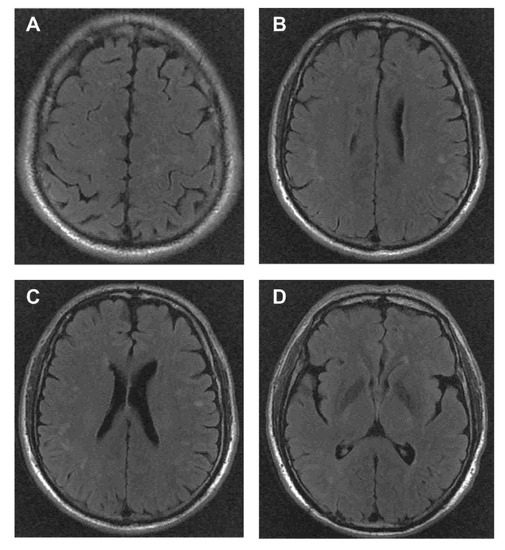

| 7 | 64/M | Decreased bilateral vision, restricted inward movement of the left eyeball, right blepharoptosis right facial hypesthesia and weak tongue movement. | + | Visual-evoked potential showed prolonged P100 latency in both eyes | Ⅲ(left) * Ⅴ *,Ⅶ (right), Ⅻ (bilateral) * | EMG of the right peripheral facial nerve showed the amplitudes of the facial nerve declining below 10% than the contralateral side | 1:100 | 0 | 0.27 | − | Bilateral lateral ventricles, bilateral frontal, temporal, parietal and occipital subcortices | Mycophenolate mofetil(MMF) | Monophasic course | Patient 1 |